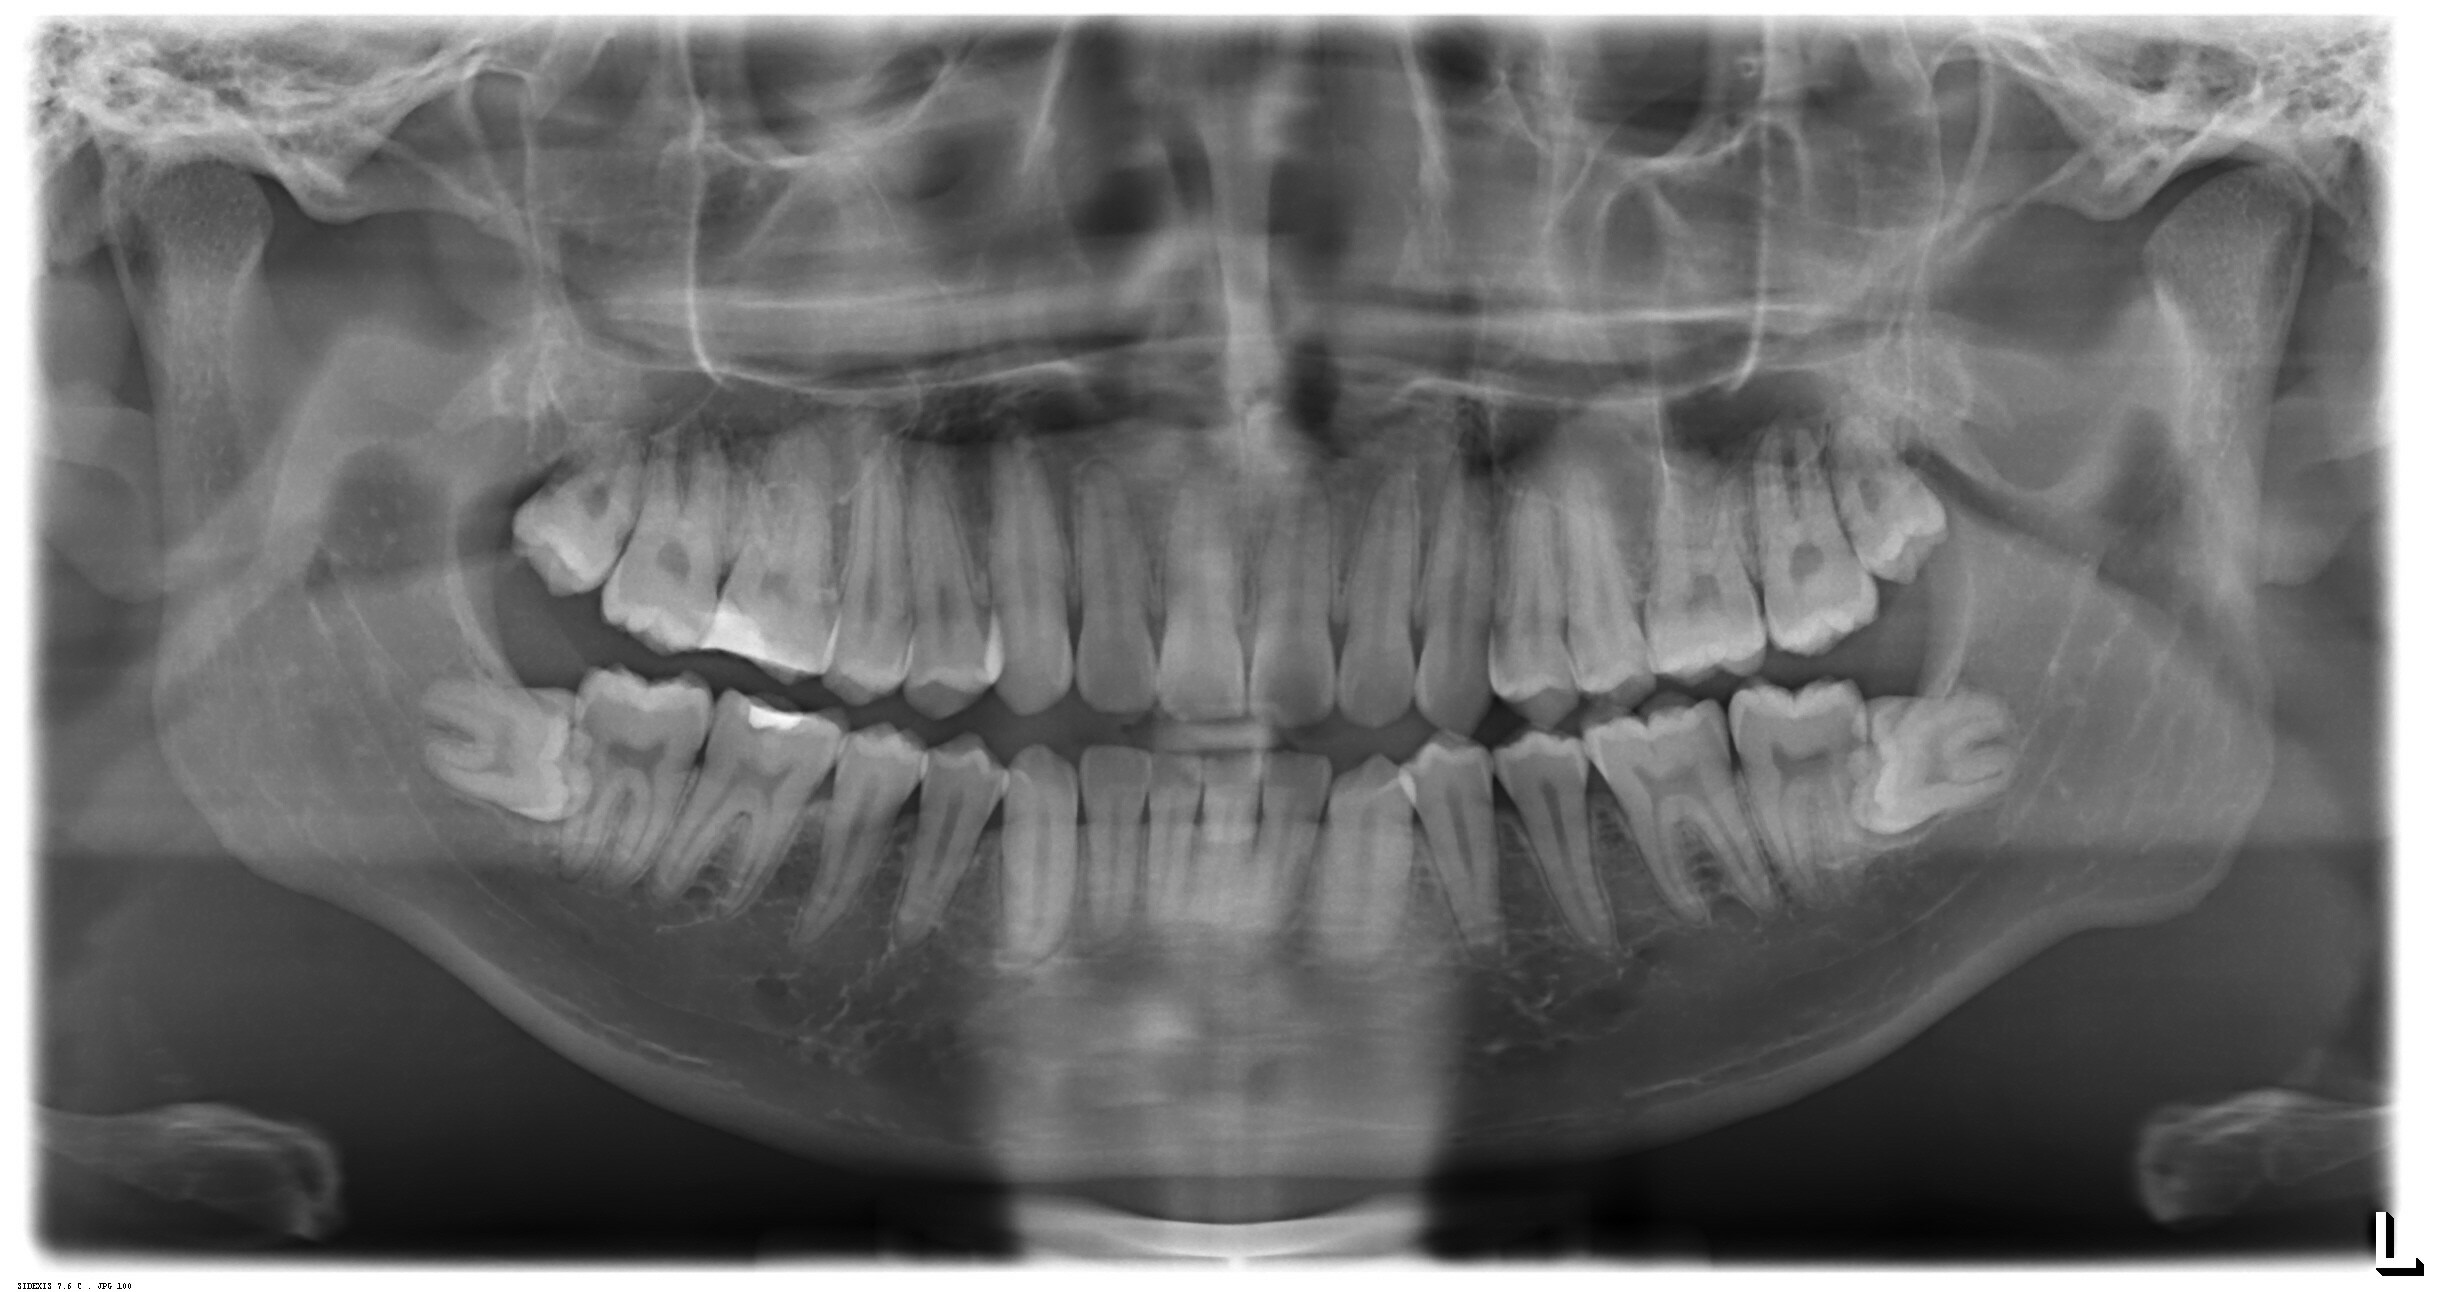

I think this is pretty common. Mine were almost the same as this.

Mine look identical to this too, they haven't moved in over 20 years and don't cause me any discomfort.

I xrayed them out 3 years ago and they just begin to murder me since Sunday.

Mine were the same. Had to get them removed when I was 14 or they would have totally screwed up the rest of my teeth

Me too! Managed to get one taken out a couple of years ago but they won't touch the other because of the nerves. Hope yours aren't causing you too much trouble

Much appreciated your support. They are giving me very bad migraine right now, i am trying to find a reliable place for surgery, some less experienced doctors i have seen seem to be not confident enough to take them out.

Yeah I sat in front of a dentist who said he was worried he'd leave my face paralysed. I was like... yeah, I'm cool with you NOT doing this. Turned out they ALL said that, so in it stays unless it causes me so much trouble I risk it. Luckily the other one was an easy removal. Hoping the best for your outcome!

Coronectomy time. I had one of my wisdoms done but it had already damaged the root of the other tooth due to NHS budget cuts.

My expirence of the coronectomy was pretty good. Half an hour OP where they remove the crown of the wisdom tooth and then stitch the root into the gum. Stitches start falling out a day or two later and it heals really quickly. I had paracetamol but probably didn't need it.

Yup, I had to go through three surgeries to remove a golf ball sized cyst in my lower jaw, that developed because I took too long to remove my impacted wisdom tooth.

If you ever notice any slight twisting of your front teeth get the wisdom teeth pulled ASAP. If they don't grow or push you're fine but you really don't want them causing your front teeth to twist as they're robbed of space. Source: Didn't notice until it was too late for mine.

Both my bottom ones are impacted like that but only one broke skin. I’m afraid to get it removed though because the doctor can’t see if it goes that deep, he said I may experience loss of feeling.

Looks like mine except i only have it to one teeth. It just endless pain.

Had to have it taken out by surgery (local dentist will not touch it). The surgeon was like you want your other three out too since you being put under general anaesthetic anyway. (Buy one get three free?) i chose not to so i still got three wisdom teeth. Currently seems to be a good idea as the molar next to the wisdom teeth taken out seems to get a small wobble the others do not have this problem. Guess they are acting like door stop for the teeth at the back.

I had the same thing happen to me but it was the upper jaw.

Mine are pretty much the same - never caused any trouble, still there some decades later so not everyone needs them extracted...

Mine are like this, never had any issues at 27 years old.

I was around your age when i first being aware of them 4-5 years ago. They just began to murder me since sunday. Extreme migraine and can't sleep at all, feel like the molar is about to explode to dust due to the pressure. I count day by day ti the weekend so i can take it out.

My bottom ones are like this. My top ones were growing in at a 45-degree angle toward the back of my mouth.

In the bottom jaw too, you will need surgery if start causing you pain. I know from experience.

I have left shoulder pain and Jaw pain for years and after my wisdom tooth surgically removed. The pain instantly goes away. Hope you find relief😊